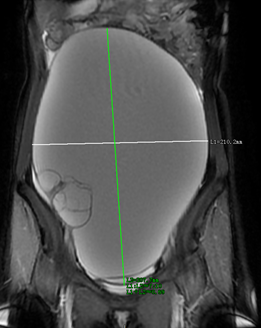

医生给**女士进一步完善了妇科超声,提示腹盆腔巨大囊性包块,范围广无法测量,上至剑突下,下至盆腔,边界不清,盆腔及腹部磁共振也提示,腹盆腔内巨大占位性病变,考虑来源于右侧卵巢,卵巢囊腺瘤可能性大。

盆腔及腹部磁共振提示,腹盆腔内巨大占位性病变